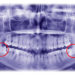

During the initial consultation, your dentist will first carry out a dental examination to determine if dental bridges are the right tooth replacement option for you. The dentist may use dental x-rays for a more comprehensive diagnosis. If you desire to have an implant supported bridge, this process will be a bit more complex than usual. It may involve the use of a CT scan as well as other advanced tests. He/she will also examine the health of your gums and other teeth to determine if you’re a good candidate for the treatment.